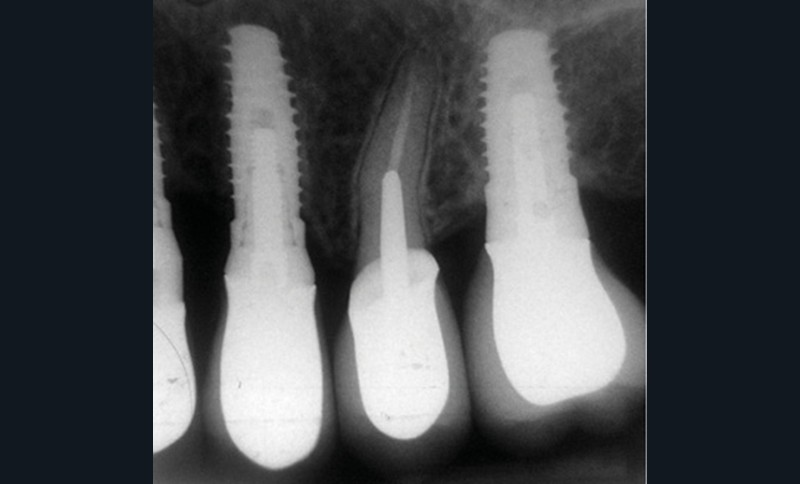

Une patiente de 64 ans, en bonne santé générale, suivie en maintenance parodontale depuis sept ans (parodontite 3B), est vue en juin 2014 pour l’extraction de sa 24 en raison d’infections endodontiques récurrentes. Le plan de traitement prévoit la pose extemporanée d’un implant et sa restauration prothétique quatre mois plus tard. La 25 est une dent couronnée et 23 et 26 sont des restaurations implantaires (fig. 1a à c). La dent antagoniste 35 est une restauration implantaire.

La radiographie péri-apicale au long cône confirme, sur la 25, un élargissement desmodontal, notamment en distal, des niveaux osseux mésio-distaux réduits par rapport aux clichés de contrôle précédents (les radiographies sont réalisées avec une technique parallèle avec des angulateurs de Rinn non personnalisés), un apex radiculaire normal et des niveaux osseux stables sur les implants adjacents (fig. 5). Le cisaillement systématique du fil dentaire lors de son passage confirme des points de contact très étroits entre 24, 25 et 26.